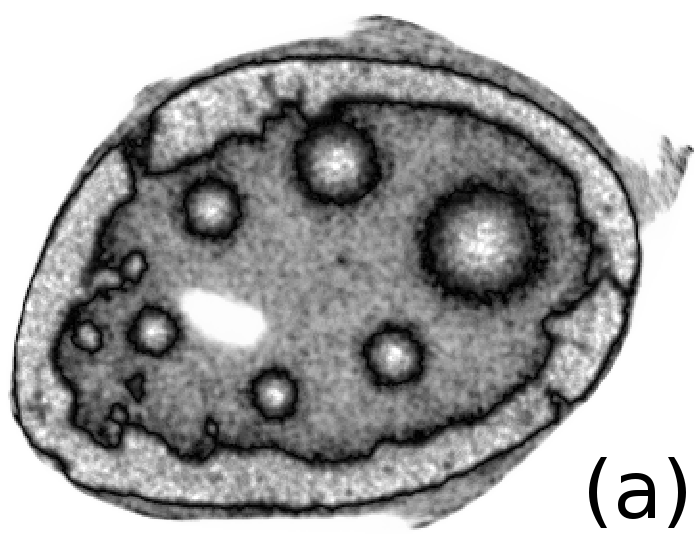

To simulate emission tomography reconstruction we designed a more realistic phantom from the high-quality X-ray scan of a mice bone. The data was acquired on a Nikon Metris Custom Bay cone-beam scanner at the Henry Moseley Manchester X-ray facility, and was reconstructed with the Feldkamp algorithm (see Fig. 7 (left)). We thresholded the obtained reconstruction and added six gaussians with various kernel widths (see Fig. 7 (middle and right)).

To simulate PET projection data we used NiftyRec [22], a software for tomographic reconstruction, providing GPU-accelerated reconstruction for emission and transmission computed tomography. The phantom size is pixels and 300 projections was simulated. Poisson noise was added to projections with an expected number of photon counts in total. Twenty noise realizations were simulated to estimate methods quantitatively. The point spread function of the PET system was modelled (with convolution of the sinogram columns with a Gaussian of full width half maximum of three pixels) in the projection and back-projection operations. No scatter was simulated in this study. For our experiments (see algorithm 2) we performed 130 MLEM iterations and 5 inner iterations (denoising step).

In Fig. 10 and 11 one can notice that the BR is very smooth for TV and TV- penalties and some long-wave oscillations can be seen in the reconstructed image with EL penalty. This result corresponds to the expected behaviour of the EL penalty. We note here that the phantoms background (see Fig. 7) is not as flat as TV and TV- penalty recovered it. Furthermore, a small size dot-like feature (approximately in the centre of the phantom) is almost smoothed out with TV and TV- recovery. However, it is visible and well recovered with EL penalty. The sharp features, overall, are reconstructed very well with MLEM-EL method and seem even sharper compare to other methods (see the bone outer rim in Fig 10).